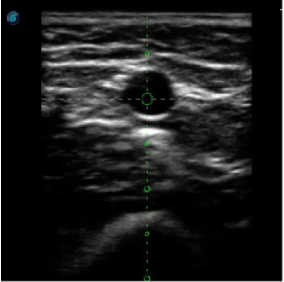

傳統(tǒng)腔內(nèi)探頭采用直柄設(shè)計(jì),在搭配穿刺架使用時(shí),手術(shù)空間小,不易操作;生殖專用的曲柄探頭,探頭柄采用彎曲成角度設(shè)計(jì),可實(shí)現(xiàn)監(jiān)視、取卵兩不誤,搭載穿刺架時(shí),可以清晰顯示穿刺針的進(jìn)針過(guò)程、深度和位置,實(shí)時(shí)監(jiān)視取卵全過(guò)程,保障取卵操作精準(zhǔn)與安全。

取卵臨床圖